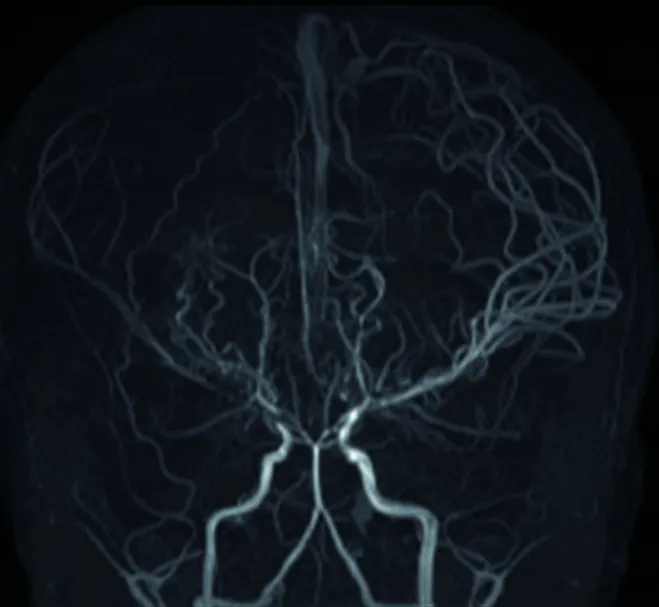

모야모야병은 뇌의 주요 혈관인 내경동맥의 끝부분과 윌리스 동맥륜이 이유 없이 좁아지거나 막히면서, 이를 보충하기 위해 뇌 밑부분에 가느다란 혈관들이 생겨나는 질환입니다. 혈관 조영술 검사에서 이러한 가느다란 혈관들이 연기가 피어오르는 모양으로 보여 '모야모야(뜻: 담배연기)'라는 이름이 붙여졌습니다.

두개 내 양측 내경동맥 말단부위나 주요 가지 동맥의 점차적인 폐쇄로 특징적인 소견을 통해 진단합니다. 뇌 혈관 조영술에서 연기 같은 미세한 혈관들이 관찰되면 모야모야병으로 진단됩니다. 뇌혈역학적 검사(SPECT)를 통해 혈역학적 스트레스 정도를 평가하고 치료 방침을 결정합니다.